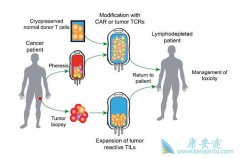

什么是 CAR-T ?CAR-T,全称是Chimeric Antigen Receptor T-Cell Immunotherapy,嵌合抗原受体T细胞免疫疗法。这是一个出现了很多年,但是近几年才被改良使用到临床上的新型细胞疗法。和其它免疫疗法类似,它的基本原理就是利用病人自身的免疫细胞来清除 ...

毫无疑问, CAR-T 的未来市场是巨大的。到目前为止,Kymriah和Yescarta这两款FDA授权的产品还远远不能满足市场的需求。据(Nat Rev Drug Discov)预计,2026年血液恶性肿瘤药物市场规模最大的几类适应症依次是复发难治性非霍奇金淋巴瘤(包括弥漫大B细胞 ...

CAR-T 作为肿瘤免疫治疗的方法之一,以其副作用小、治疗效果显著,被称为继手术、化疗、放疗后的第四大肿瘤治疗手段,其正逐渐成为未来肿瘤治疗的新方向。但是,它也有着不可避免的副作用及技术难题。(1)实体肿瘤效果较差。目前,治疗效果最成功的当 ...